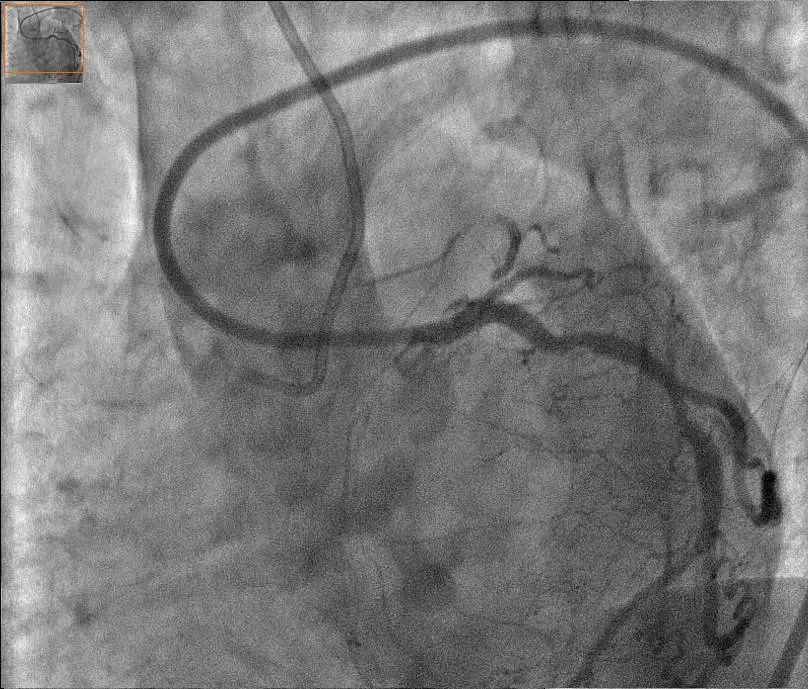

Case : CTO of Ostial LAD

Baseline CAG

Final result